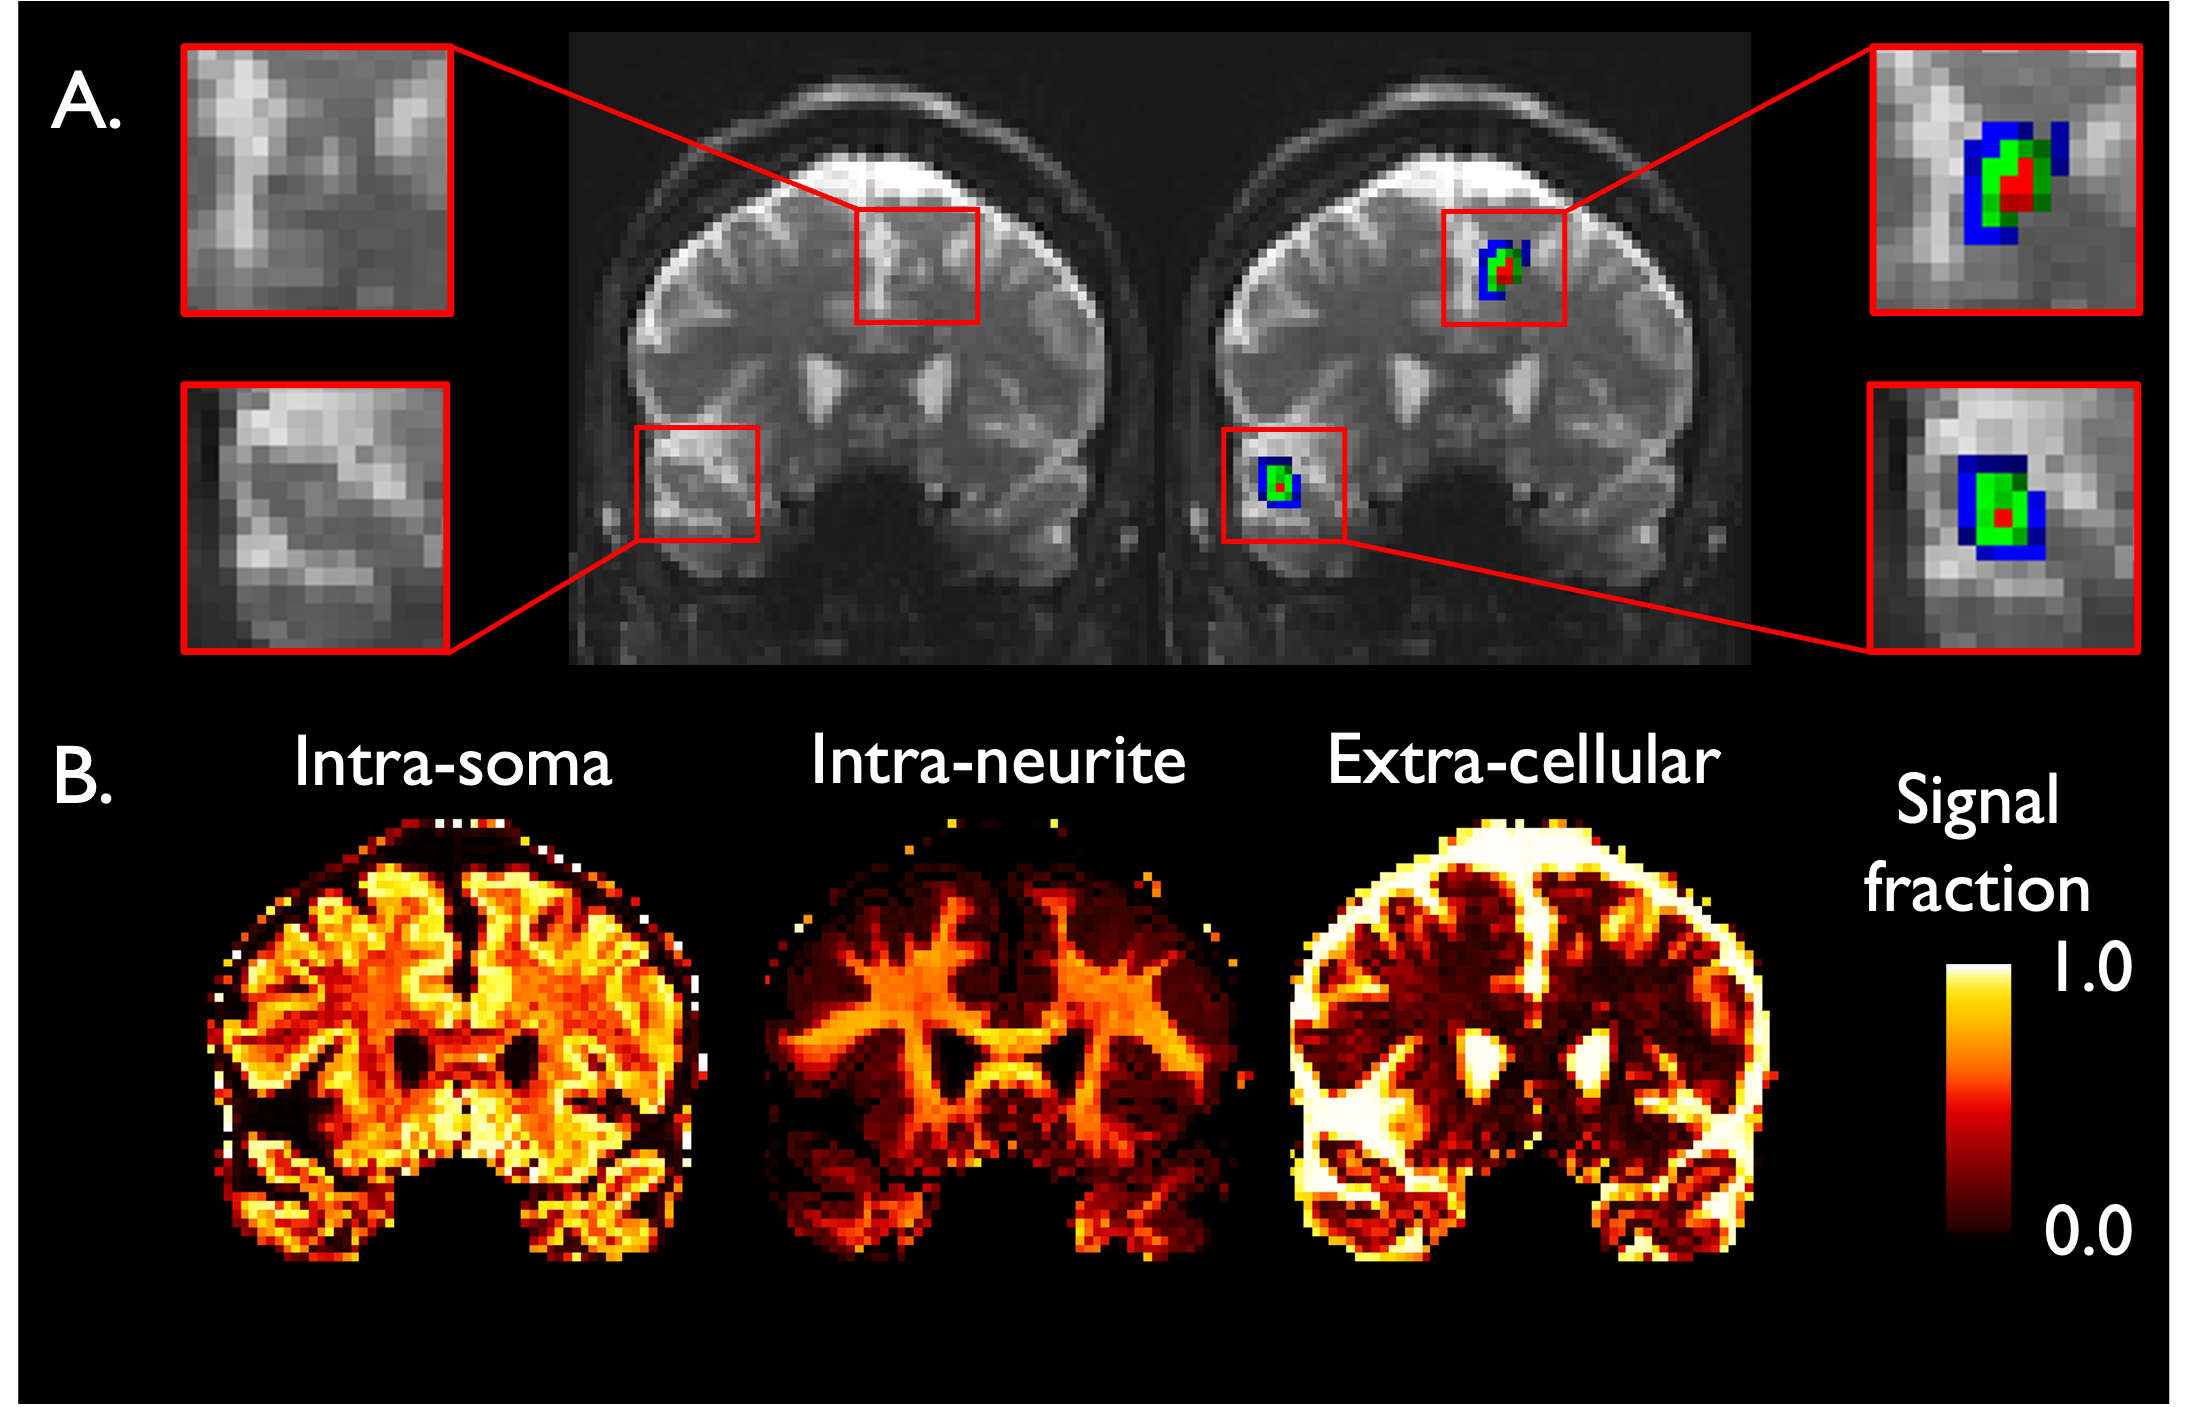

该研究提供了多发性硬化症(MS)患者皮层病变中细胞体丢失的活体证据。研究者对MS患者和健康对照组进行了高场强MRI扫描,并使用了扩散模型来分析皮层病变区域的细胞内信号。结果显示,与周围区域和正常外观的皮层相比,MS患者的皮层病变区域显示出细胞内信号分数的减少。讨论部分指出,高梯度扩散MRI有潜力在活体中检测皮层细胞体丢失,这可能对认知功能有重要影响。结论强调了高梯度扩散MRI在MS患者皮层病变评估中的应用,并可能对认知功能下降的风险评估有所帮助。

ef4a0ed274b5790d61c7b32996ae0262.png

代表性的冠状切面图像展示了多发性硬化症中皮层病变在扩散空间(A)红色对应病变核心,绿色对应内周病变层,蓝色对应外周病变层)和SANDI测量(B)的情况。信号分数范围从0到1。